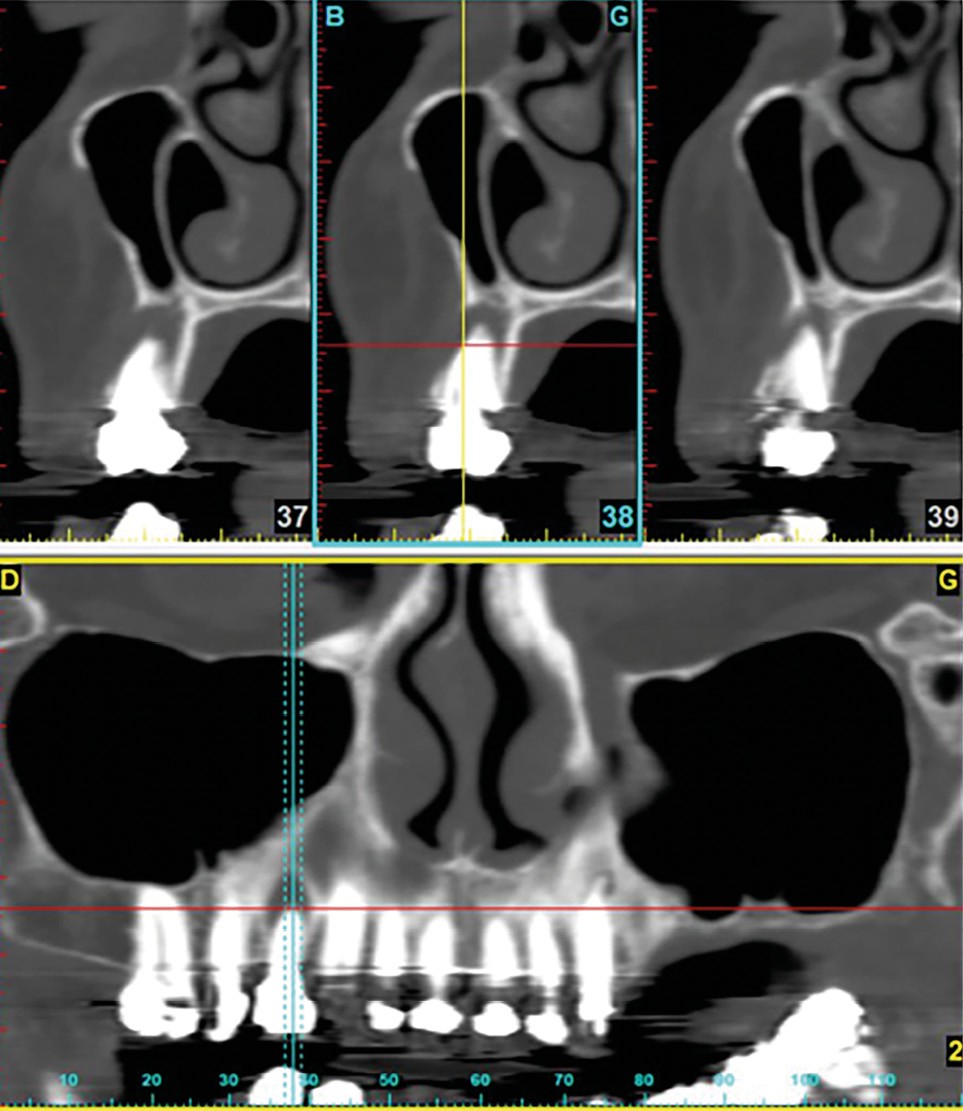

Le nombre de patients traités pour l’ostéoporose notamment est important parmi la patientèle des cabinets dentaires. La question sur la possibilité de pose d’implants est récurrente chez ces patients. Ainsi, il est important de rappeler qu’il faudra systématiquement rechercher la prise éventuelle d’IRO au cours de l’interrogatoire médical. Les patients ne faisant pas toujours le lien avec nos gestes pourront omettre de le signaler spontanément.

Si les recommandations et les différents auteurs s’accordent depuis longtemps pour contre-indiquer la pose d’implant dans le contexte malin, celle-ci n’est pas contre-indiquée chez un patient traité par IRO dans un contexte bénin [9]. De nombreuses publications ont montré des taux de succès comparables à ceux de la population générale. Cependant, ces données sont à considérer avec discernement car le recul et le niveau de preuve scientifique sont encore faibles [10]. Ainsi, il semble raisonnable de ne pas réfuter de principe la solution implantaire chez ces patients. Mais il conviendra de les informer clairement du rapport bénéfice/risque. Trois points semblent indispensables pour aider à la décision. Il s’agira d’évaluer la durée du traitement (plus ou moins 3 années), les facteurs de comorbidité (diabète, corticothérapie notamment) et l’invasivité du geste chirurgical (implant unitaire ou multiple, nombre de sextants concernés) (fig. 3). Dans tous les cas, les alternatives thérapeutiques devront être proposées et discutées avec le patient.